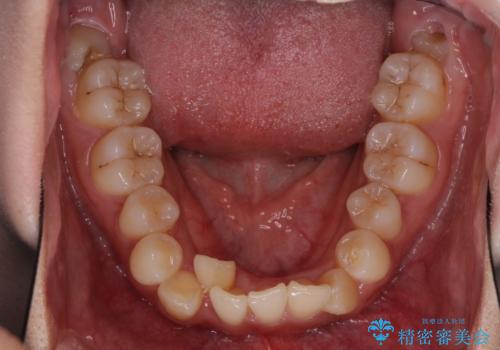

- 前歯のデコボコと残っている乳歯の部分へのインプラント治療を希望して来院された患者様です。

当初は目立たない上下裏側矯正を希望されていましたが、歯並びの悪さによる磨き残しが多く、歯肉炎が認められたため、より清潔な環境で治療を進められるインビザラインを選択することとしました。

前歯のデコボコが強かったため、上の奥歯を後方に動かす量が多くなり、結果として2年以上の治療期間を擁することとなりました。

歯並びが整ったことで治療前に認められた歯肉炎は全くなくなり、患者様には大変満足していただきました。